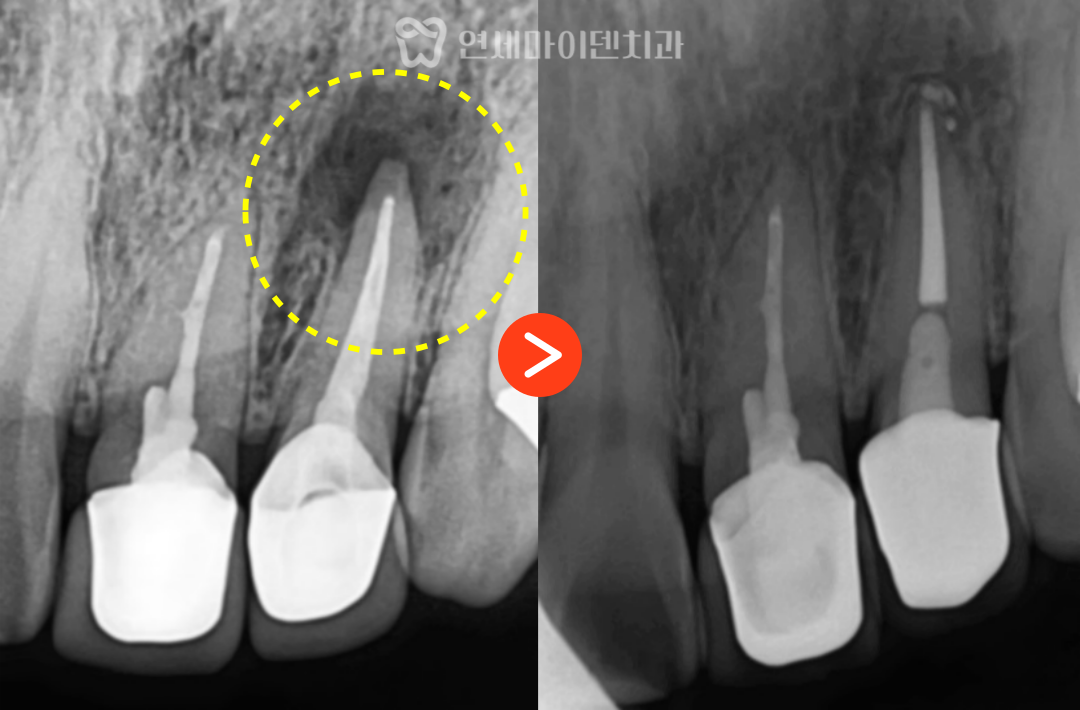

치료 전 엑스레이를 보면

앞니는 이미 신경치료 후 크라운까지

마무리된 상태였습니다.

다만 한쪽 치아의 뿌리 끝에만

둥글게 뼈가 녹아 있는

큰 염증이 관찰되었습니다.

치료 후 6개월, 염증의 변화

재신경치료 후 약 6개월이 지나자

뿌리 끝에 있던 염증은 점차 줄어들고

뼈가 다시 차오르는 양상이 확인되었습니다.

결과적으로 치근단 절제술이나 발치 없이

재신경치료와 크라운만으로

치아를 보존할 수 있었습니다.